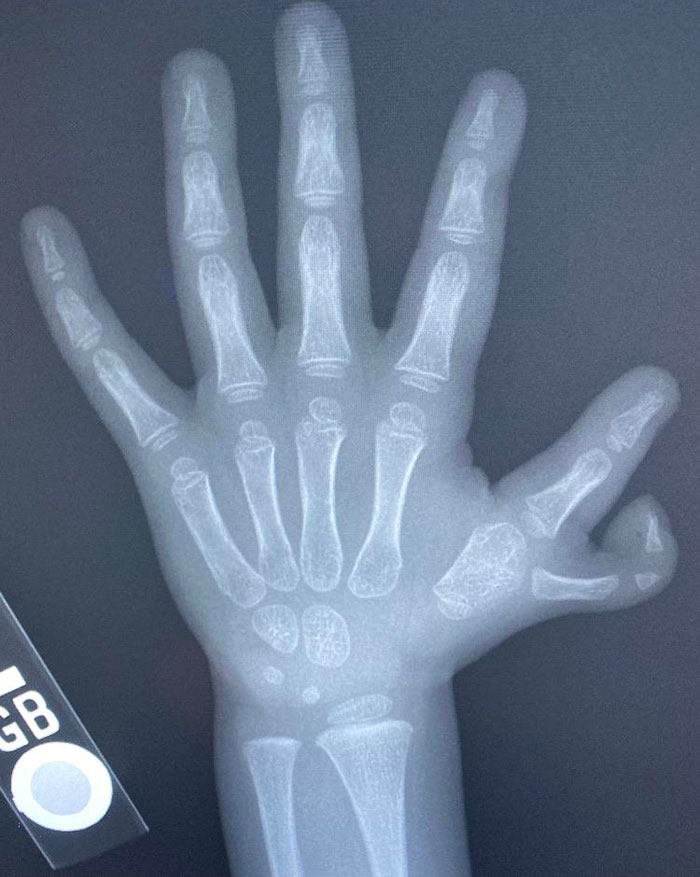

Polydactyl Claw X-Ray